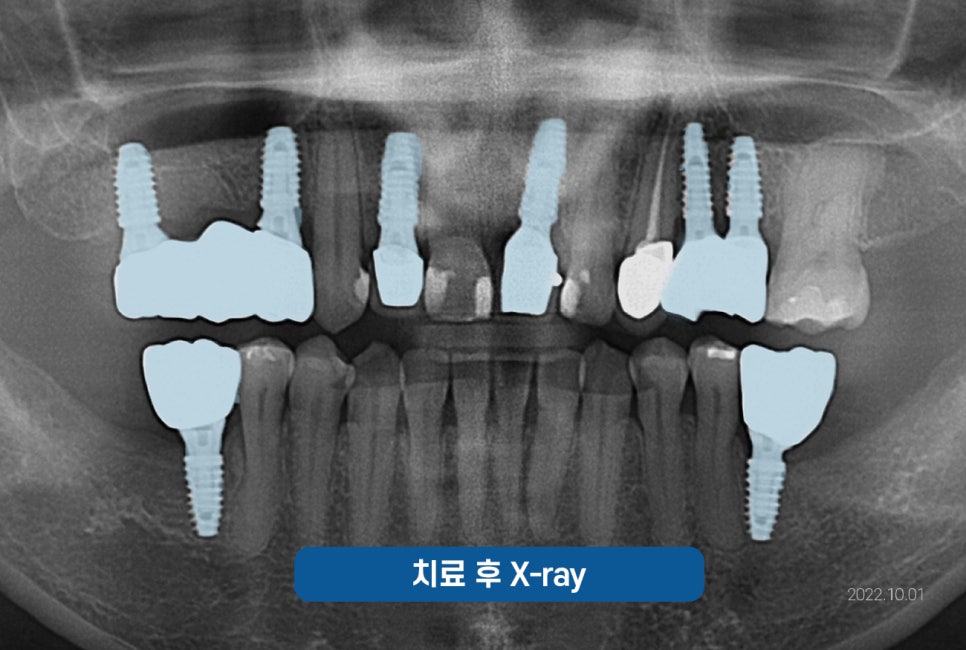

마무리 된 사진

함께 보도록 하겠습니다.

🔽

위 사진은 임플란트 수술까지

마무리가 된 사진인데요.

개인의 잇몸상태를 분석하여

식립각도와 위치를 신경써서

안정적인 임플란트를 심어드렸고

반영구적으로 사용할 수 있도록

도와드렸습니다.